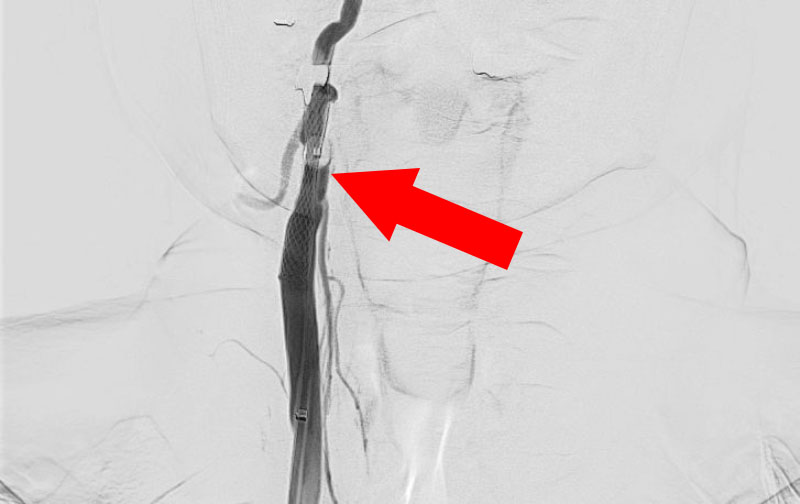

1337

'23年2月6日

右頚部内頚動脈狭窄症

70代

大阪府の病院

手術写真

治療

前

中

後

手術日